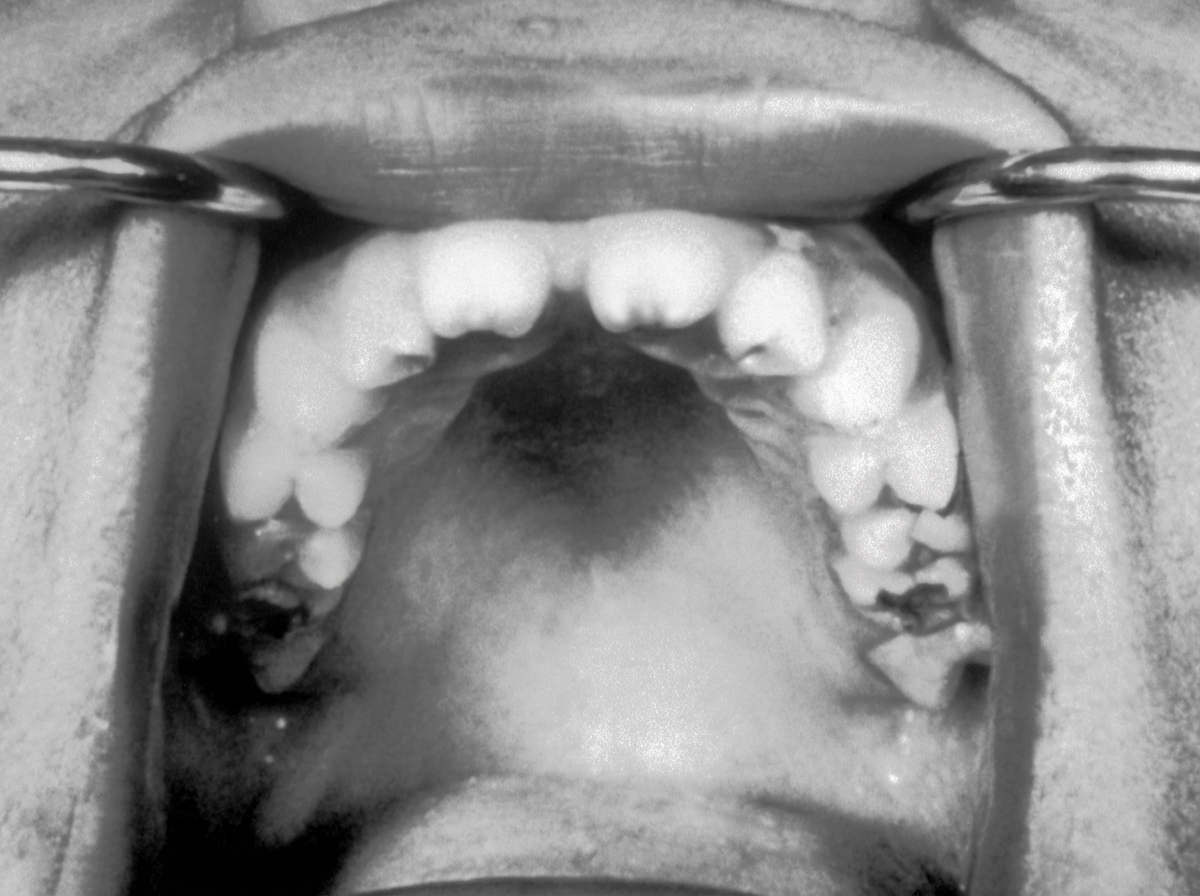

The teeth abnormality shown in the image is seen in which of the following diseases?

Explanation: ***Congenital Syphilis*** - The dental abnormalities shown are likely **Hutchinson's teeth** (notched, peg-shaped incisors) and **mulberry molars** (dome-shaped first molars), pathognomonic of congenital syphilis. - These findings are part of **Hutchinson's triad** which includes interstitial keratitis, eighth nerve deafness, and Hutchinson's teeth. *Cleidocranial dysostosis* - Dental abnormalities include **delayed tooth eruption**, **supernumerary teeth**, and **impacted permanent teeth**. - Associated with **absent or hypoplastic clavicles** and **delayed fontanelle closure**, not the specific tooth morphology seen in the image. *Congenital Rubella* - Dental manifestations are minimal and include **delayed tooth eruption** and **enamel defects**. - Primary features are **cataracts**, **cardiac defects**, and **sensorineural hearing loss**, not characteristic dental malformations. *Congenital hypothyroidism* - Causes **delayed tooth eruption** and **prolonged retention of deciduous teeth**. - Associated with **growth retardation** and **mental retardation**, but does not cause the specific morphological tooth changes shown.